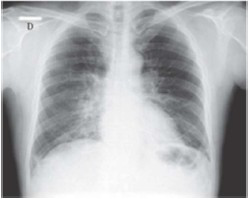

Paciente do sexo masculino, de 58 anos, empresário, natural e procedente de Goiânia – Goiás, procurou unidade de pronto atendimento relatando que há uma semana iniciou quadro gripal caracterizado por febre aferida (38,5 ºC), dores no corpo, coriza e obstrução nasal. Três dias depois, passou a sentir muito cansaço e mal-estar. Nesta ocasião procurou atendimento em unidade primária, onde realizou radiografia de tórax e recebeu o diagnóstico de pneumonia. Foi medicado com amoxacilina clavulanato por via oral, com a recomendação de retornar caso piorasse. Continuou cada vez mais cansado, retornando ao serviço de emergência novamente dois dias depois. Antecedente de hipertensão arterial em uso de losartana 50mg duas vezes ao dia. Nega outras comorbidades. Nega tabagismo. Ao exame físico, mostrava-se em regular estado geral, corado, hidratado, anictérico, cianótico +/4, dispneico +++/4, sem linfonodomegalias. Temperatura axilar de 36,8 ºC. Glasgow 15. Aparelho cardiovascular: bulhas rítmicas normofonéticas sem sopros, frequência cardíaca 110 bpm, pressão arterial de 130x90 mmHg. Aparelho respiratório: frequência respiratória de 32 incursões por minuto, com uso de musculatura acessória, ausculta pulmonar com estertores crepitantes difusos em ambos os pulmões. SpO2: 85% em ar ambiente. Abdome: nada digno de nota, sem visceromegalias. Extremidades sem edema. Peso 78 kg; altura 1,65m. Foi realizada uma nova radiografia de tórax (imagem abaixo) e coletados exames laboratoriais, incluindo hemoculturas e perfil virológico. Gasometria arterial colhida na entrada evidenciou: pH = 7,53; PaCO2 = 30 mmHg; PaO2 = 50 mmHg; bicarbonato = 24 mEq/L; base excess = +0,5 mEq/L; e SaO2 = 85%.